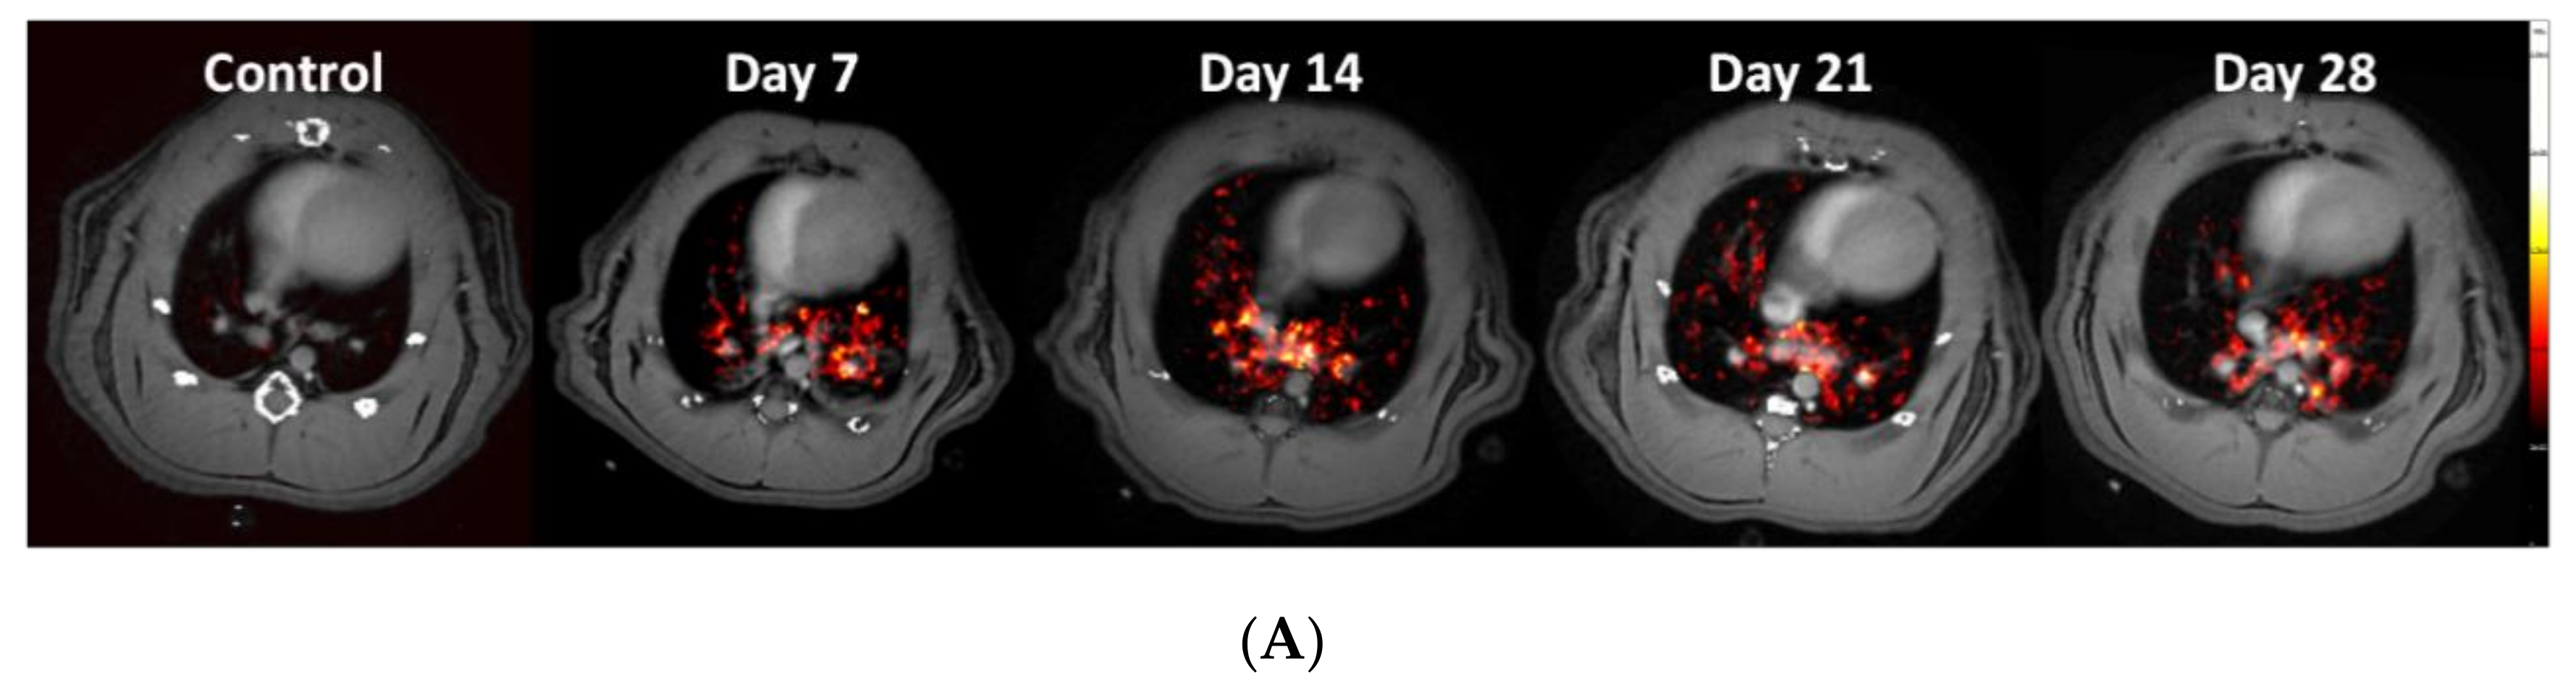

3.3. Using the PET-tracer CBP-Cu64 to Assess Non-Cross-linked Collagen-I

3.4. Molecular Assessment of Collagen Production and Cross-Linking